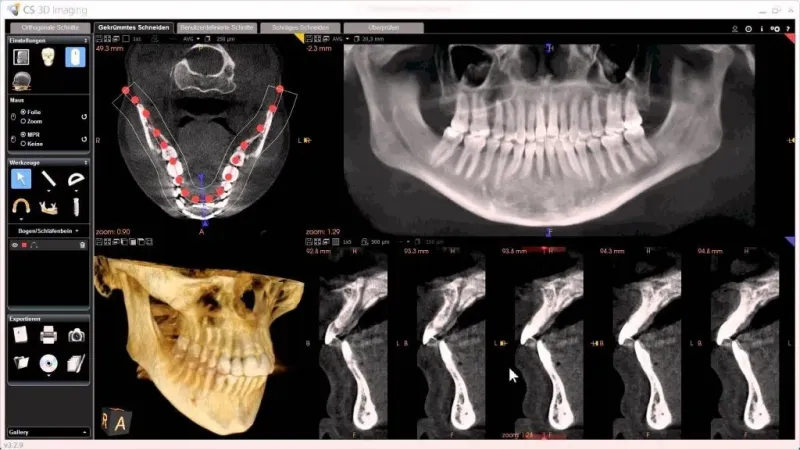

- Khách hàng có thể thấy rõ cấu trúc răng, xương hàm, dây thần kinh,… một cách chân thực nhất chỉ bằng hình ảnh 3D với độ phân giải cao, siêu rõ nét.

Chụp CT ở Anh Dental cho ra hình ảnh 3D tổng quát sắc nét nhất